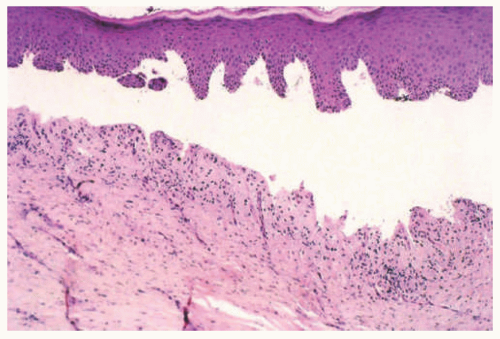

DEB is caused by a split just below the lamida densa, with histologic sections demonstrating a subepidermal blister cavity (Figure 4-16). As with other forms of EB, the lesions

usually lack an inflammatory infiltrate, although chronic inflammation and dermal scarring may accompany the lesions because of continuous skin damage over the course of the disease.10 The numerous subtypes of DEB cannot be distinguished on histologic examination alone, and a specific diagnosis relies on correlation with the clinical and genetic features of the disorder.1

Milia formation is another well-known histopathologic finding associated with DEB. Milia are small dermal cysts lined by squamous epithelium and containing loose keratin (they are essentially miniaturized epidermal inclusion/epidermoid cysts) (Figure 4-17). In one case report, multiple milia was the presenting skin manifestation of DEB.13 However, any disorder that causes repeated skin damage may result in milia formation, making the finding of milia nonspecific (the lesions of EBA, eg, also frequently show milia). Immunomapping studies show the presence of KRT5 and KRT14, laminins, and type IV collagen along the roof of the blister. On ultrastructural examination, anchoring fibrils are often altered or reduced and may even be absent in severe recessive dystrophic forms of EB.